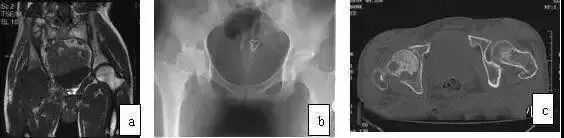

应用MRI检查,则鉴别不难。MRI示广泛滑膜病变(T1WI、T2WI均为低信号),病变侵犯广泛(股骨头颈、髋臼)是其特点,CT扫描可见骨皮质侵蚀,累及髋臼和股骨头、颈部,与ONFH鉴别不难(图10)。

图10 男,28岁,右髋钝痛二年,关节活动明显受限,诊断为色素沉着绒毛结节滑膜炎。(a)MRI的T1WI示右股骨头、颈弥散性低信号;(b)X线片示右髋股骨头及髋臼破坏,关节间隙变窄;(c)CT扫描示股骨头颈骨破坏